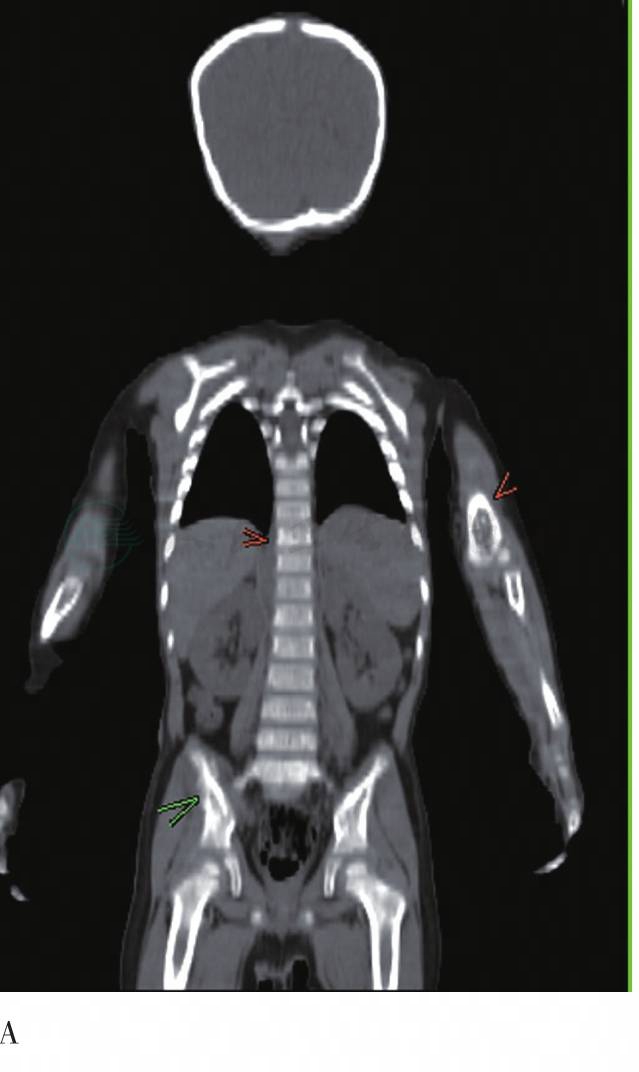

图4 脊柱冠状面

A. CT;B. PET;C. PET/CT融合图。颅骨、肱骨、髂骨、脊柱等多发弥漫性、局限性FDG摄取增高灶,同机CT骨质局部破坏,SUVmax为8.5

颅骨、肱骨、骨盆、脊柱、股骨等处多发局限性FDG摄取增高灶,同机CT骨质破坏或密度不均匀,摄取最高处SUVmax为8.5。